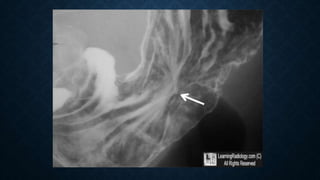

This document provides an overview of x-rays for medical students, covering topics such as ensuring x-rays are well-aligned, exposure levels, common artifacts and anatomical features, abdominal x-ray positions and views, and specialized x-rays including barium swallows, enemas, and tests to examine the esophagus, small bowel, biliary tree, and kidneys.